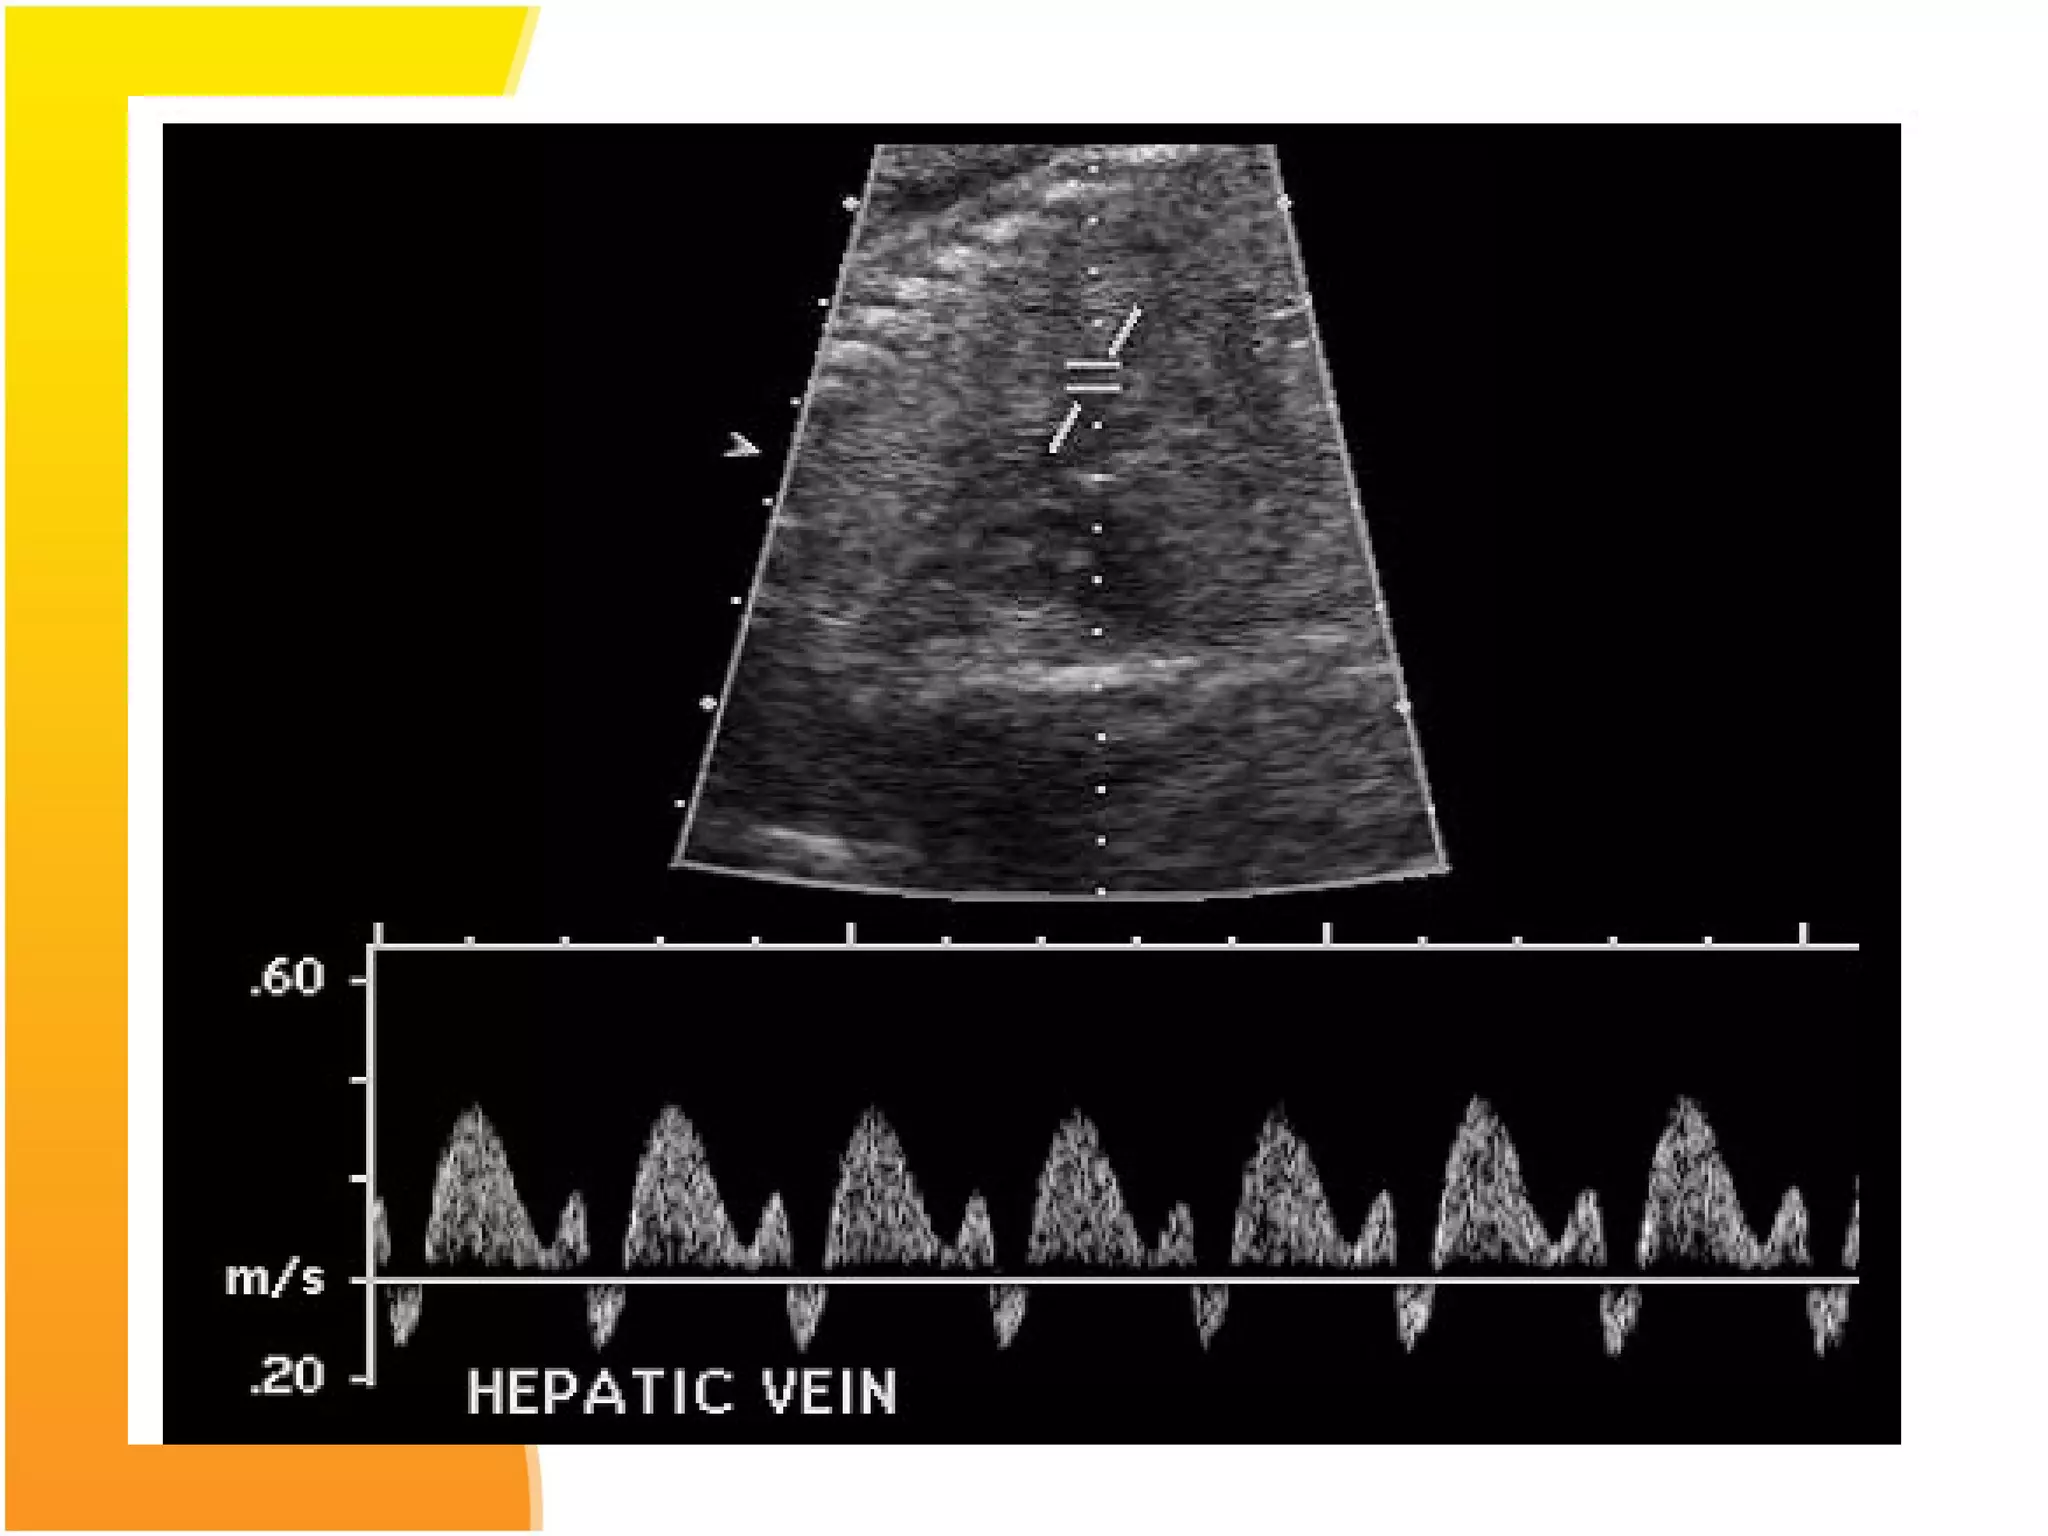

Middle cerebral artery Doppler- in a

normal fetus has relatively little flow

during diastole. Increased resistance to

blood flow in placenta results in

redistribution of cardiac output to

favour cardiac and cerebral

circulations leading to increased flow

in the diastolic phase with decreased

S/D ratio.

Normal Flow velocity waveforms of middle Cerebral Artery

Doppler